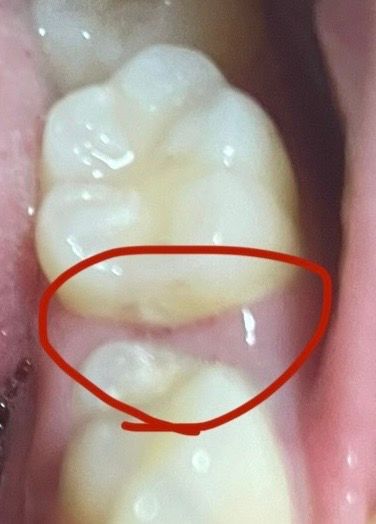

잇몸이 파인 걸까요?? (사진첨부)

반대쪽 어금니 잇몸보다 유난히 저 부분이 어둡길래 한번 손잡이 있는 치실로 긁어봤거든요.(긁기 전엔 사진 보다는 덜 어두웠었어요.) 근데 음식물 같은 것 들이 조금 나오더니 깊이가 생긴 것처럼 더 어두워졌어요. 충치가 생긴 건 아닌가해서 긁어봤더니 이에 뭐가 난 건 아니고 잇몸에 깊이가 있는 틈이 생긴 것 같아요.

사진상으로 보면 잇몸에 살짝 상처가 생긴거 같습니다. 치실이나 양치를 너무 강하게 해서 생긴게 아닐까 생각됩니다.

사진만으로 평가하기에는 양치질 등으로 인해서 해당 부분이 자극을 받아 일시적으로 발적된 것으로 예상됩니다.

해당 사진의 선명도가 높지 않아 정확한 판단을 하는데 있어 어려움이 있습니다. 충치일 가능성도 있으나 치아와 잇몸 사이의 공간이 어둡게 보일 가능성도 배제할 수 없어 보입니다. 현재로서는 정확한 판단을 위해서 치과 방문을 하는 것이 가장 좋으며, 조금 더 높은 해상도의 사진을 올려주시면 판단에 도움이 될 것으로 보입니다.

잇몸이 자극을 받아서 일시적으로 붉어진 것으로 보입니다. 만약 해당부위가 붓고 통증이 있는 경우는 치과진료를 받길 권하며, 이물질을 억지로 제거하기 보다는 치과에서 검진 및 스케일링을 받길 권합니다.